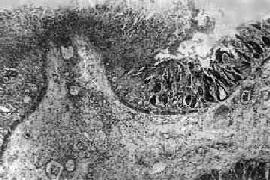

1.急性细菌性痢疾 病变初期呈急性卡他性炎,表现为粘液分泌亢进,粘膜充血、水肿、点状出血、中性粒细胞及巨噬细胞浸润,粘膜上皮坏死脱落后形成表浅糜烂。粘膜下层也可见炎性反应,但程度较轻。病变进一步发展乃成为本病特征性的假膜性炎,表现为粘膜表层坏死,同时在渗出物中出现大量纤维素,后者与坏死组织、中性粒细胞、红细胞和细菌一起形成假膜(图18-22)。假膜首先出现于粘膜皱襞的顶部,呈糠皮状,随着病变扩展可融合成片。假膜一般呈灰白色,如出血严重或被胆色素浸染时,则可分别呈暗红色或灰绿色(图18-23)。大约在发病后一周左右,在中性粒细胞破坏后释出的蛋白溶解酶作用下,纤维素和坏死组织发生溶解液化,而使假膜成片脱落,形成大小不等、形状不一的溃疡。溃疡多数浅表,甚少穿破粘膜肌层,但亦偶有深达肌层引起穿孔导致腹膜炎者。当病变趋向愈复时,肠粘膜的渗出物和坏死物逐渐被吸收、排出,组织的缺损经再生而修复。浅小的溃疡愈合后无明显瘢痕形成,深而较大的溃疡愈合后可形成浅表瘢痕,很少引起肠腔狭窄。

图18-22 细菌性痢疾

结肠粘膜表层坏死并有白细胞和纤维素性渗出物